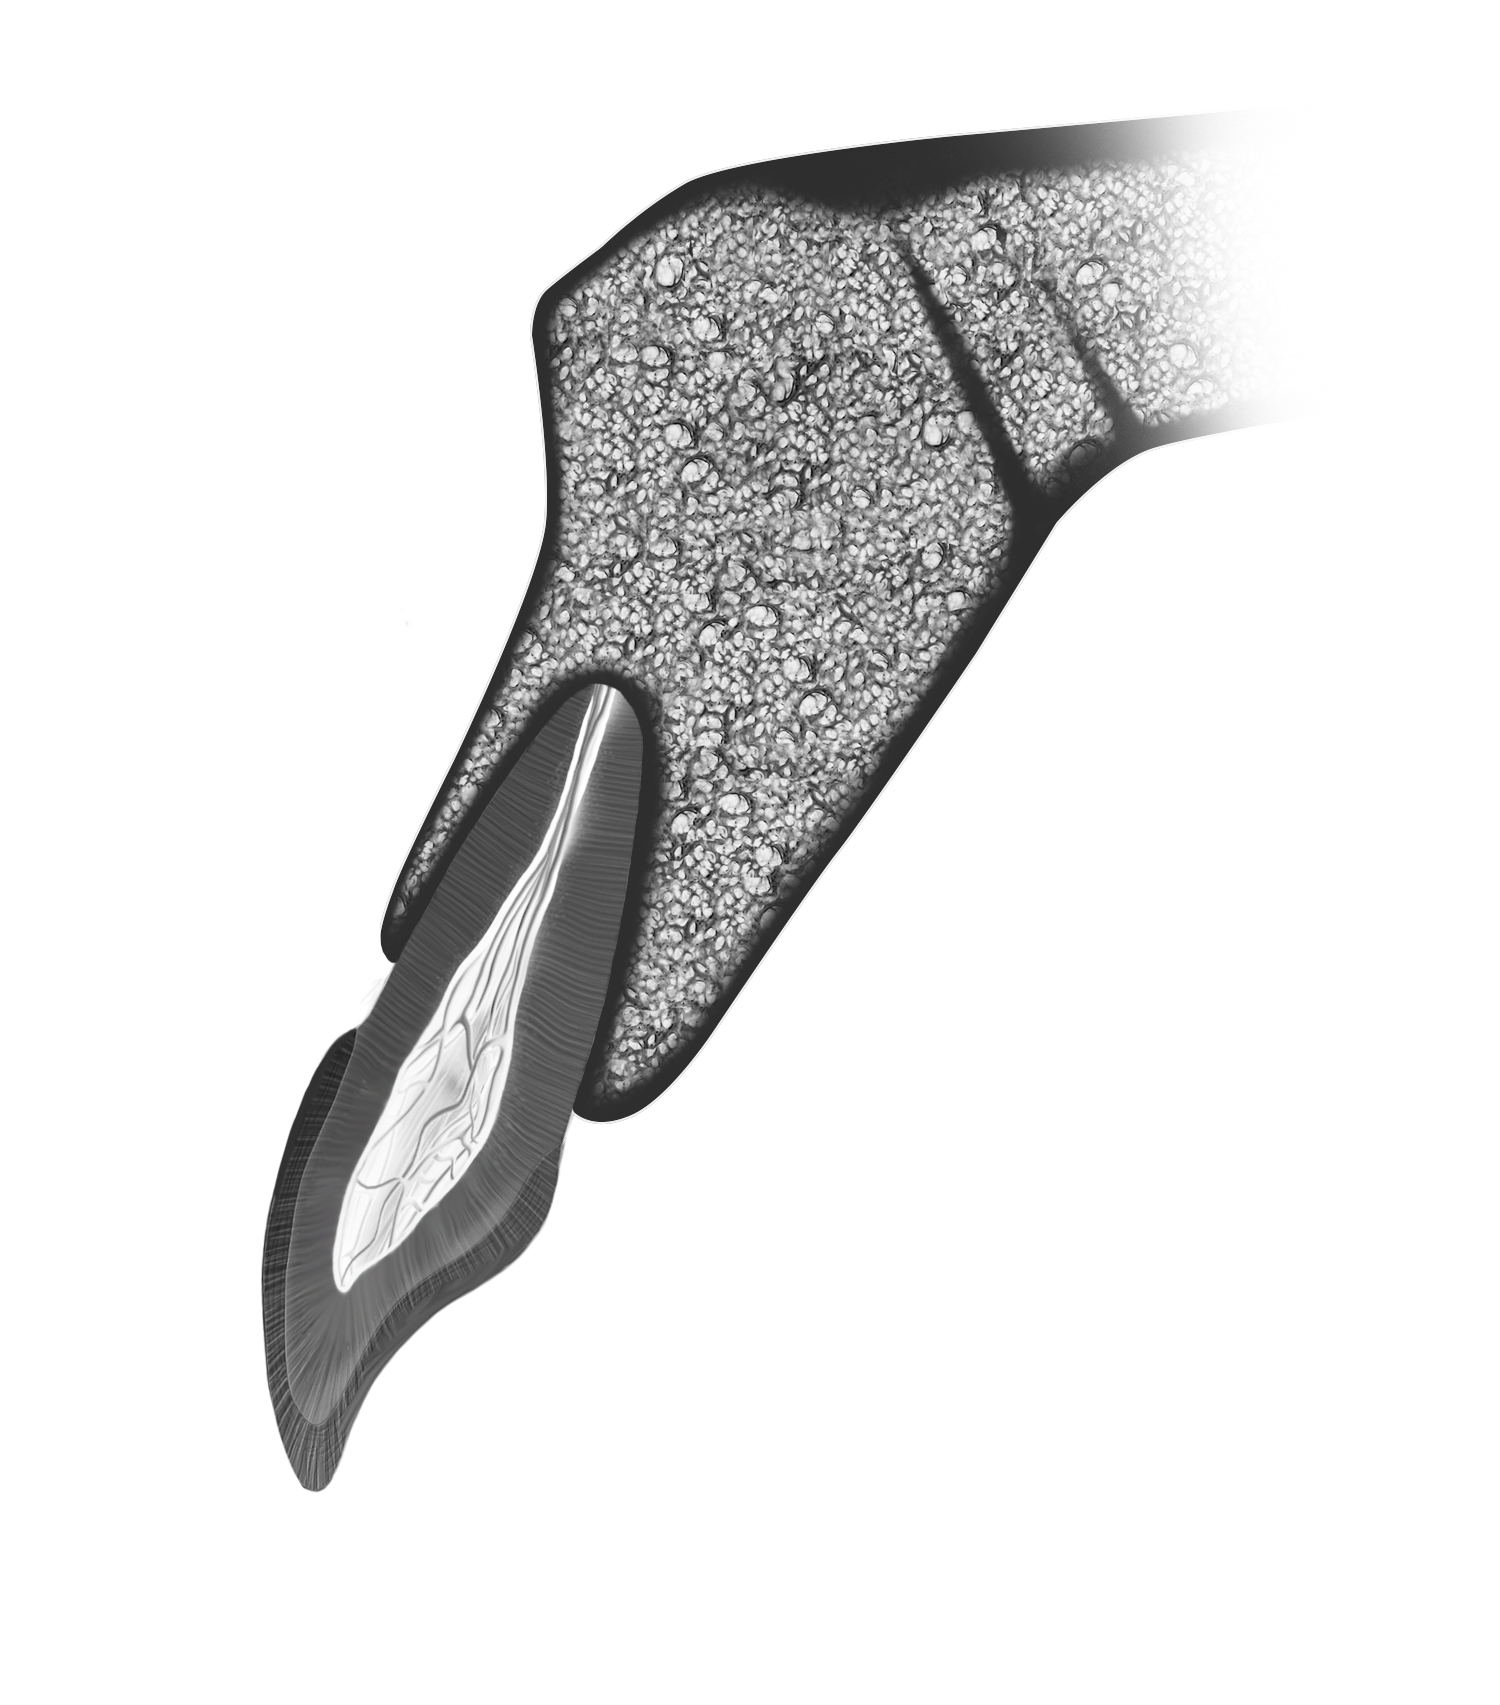

Fig 1. The most common position of the tooth in the anterior maxilla, with the root in intimate contact with the buccal cortical plate. Note the biaxial relationship between the tooth crown and root.

Figure 1

The human alveolus is an intricate, nonuniform structure that encases the complex anatomy of the human dentition and critical anatomic landmarks. Teeth, particularly those in the anterior, display a slight disparity between root and crown angulations (Figure 1), imposing obstacles in implant dentistry. The replacement of lost teeth has long been a challenge. The contemporary treatment of choice in many cases is the implant-supported prosthesis (ISP), which has been in use since the discovery of osseointegration by Professor Per-Ingvar Brånemark in the 1960s.1 An osseointegrated implant provides a direct and relatively rigid connection of the implant to the bone.2 Careful surgery is required to place a titanium fixture in the correct 3-dimensional position in bone to support an esthetic and functional tooth replacement.

Kan et al9 showed that in 76% to 86.5% of cases, the tooth position in the anterior maxilla is most often positioned very close to the buccal plate (Figure 1). This plate and the roots are proclined forward from the nasal spine. Consequently, together with the crown–root angulation offset, a straight implant fixture is unlikely to be able to fully satisfy both root and crown positions, particularly if the prosthesis is to be screw retained.

Howes et al40 described the research and development of an implant with 12-degree subcrestal angular correction, originally designed to overcome the anatomic constraints of the anterior maxilla for screw retention. In this unpublished study, the authors recognized the conflict between the surgical and restorative objectives in ISPs in the anterior maxilla. The morphology of the anterior maxilla was analyzed on lateral cephalometric radiographs of 30 class I to III maxillae. In addition, the differences between the axes of the crowns and roots of 30 anterior teeth were assessed, including canines and lateral and central incisors. The root–crown offset ranged from 8 to 12 degrees (Figure 3), and the angle between the buccal plate and ideal screw axis ranged from 25.6 to 30 degrees (Figure 4). The resultant fixture design had a 12-degree angular offset between implant body and prosthetic platform, with a 0.6-mm body thread pitch to minimize apical travel per rotation. This implant is able to accommodate these angulation constraints due to the combined taper and head angulation.